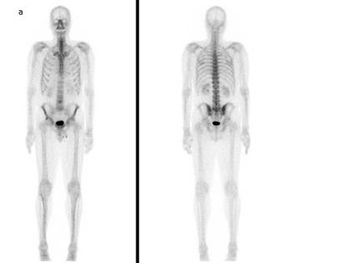

Nuclear medicine uses radioactive substances, called radiopharmaceuticals, in the diagnosis and treatment of a range of diseases. These substances are chosen or especially developed to be taken up predominantly by one organ or one type of cell in the body. Nuclear medicine offers unique diagnostic information in oncology, cardiology, endocrinology, neurology, nephrology, urology and other areas. Such information is not obtainable, or obtainable only with less accuracy, by other modalities. For nuclear medicine diagnostic procedures, trace amounts of radiopharmaceuticals are administered to patients through injection into veins (intravenous), skin (intradermal) or tissues (intraparenchymal) as well as breathing in (inhalation) or eating/drinking (ingestion). After intake, the function, or physiology, of various tissues, organs or organ systems can be demonstrated. For example, in cancer patients, nuclear medicine imaging can be used for diagnosis (i.e. is a cancer present), staging (i.e. how far has it spread), assessment of response to therapy or of possible disease recurrence. Nuclear medicine cameras are now commonly combined with a CT unit (e.g. hybrid SPECT/CT and PET/CT) which allows precise anatomic localisation of pathology. (Figure 1, Figure 2a, 2b)

Nuclear medicine procedures for treatment are non-invasive and present no risk of direct complications to patients, but limited to several well-established situations where killing hyperfunctioning or malignant cells is important (for example hyperthyroidism, cancer of the thyroid, degenerative and inflammatory diseases of joints, palliative treatment of metastases to the skeleton). In addition, there are many studies showing significant potential for radio-labelled antibodies and receptor-avid peptides to be used in the treatment of several malignancies.